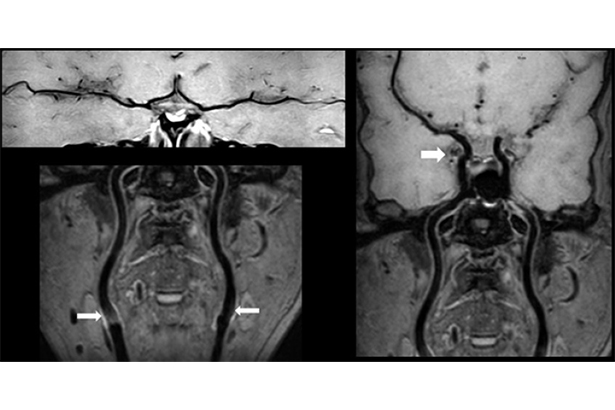

高分辨HOP MRA成像同時使用亮血和黑血兩種血管成像技術,一次掃描獲得三組圖像(TOF、FSBB、HOP),可以進行管腔狹窄評估,得到遠端血管信息 ,同時實現血管壁斑塊成像。